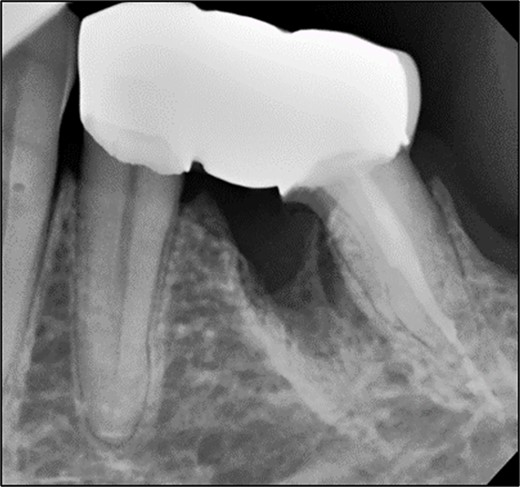

A 59-year-old male patient presented with a complaint of pain while biting on his lower left posterior teeth. Clinical examination revealed an extensive amalgam restoration on the lower left first molar (tooth 36) with a fractured restoration and secondary caries on the lingual aspect. The tooth was non-responsive to thermal testing and electrical pulp sensibility testing (EPT) and was tender to percussion. Radiographic examination showed radiolucency beneath the restoration on the mesial root surface, indicative of caries, along with furcation involvement and peri-radicular radiolucency. The tooth was diagnosed with pulpal necrosis and symptomatic apical periodontitis associated with extensive root caries (Fig. 6 and 7).

Periapical radiograph of tooth 36 shows large radiopacity, indicating a restoration on the crown extending to the mesial root surface. Radiolucency was detected beneath restoration on the mesial root surface, indicating caries. Peri-radicular radiolucency was observed in the furcation region.